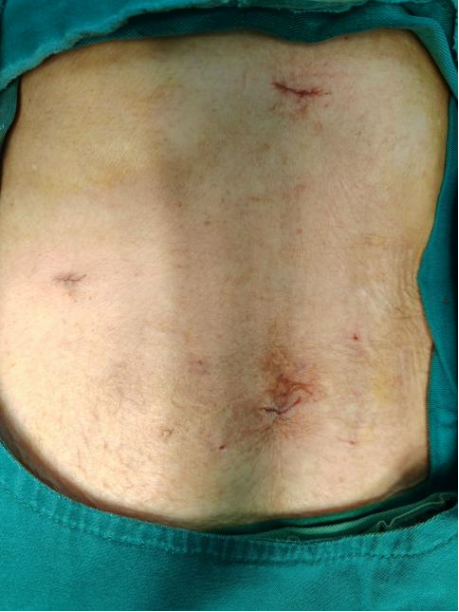

(术前腹部CT图片)

张婆婆被胆囊结石困扰了八年,平时疼起来坐立难安,生活特别受影响。这次因为急性胆囊炎、胆源性胰腺炎突然发作住院,病情已经很严重了。更让医生们操心的是,张婆婆还患有冠心病、甲亢转甲减、低蛋白血症、支气管扩张症,而且双耳几乎听不见,跟她沟通特别困难。

这些毛病加在一起,让必须做的胆囊切除术风险大大增加。“我母亲都84岁了,一身的病,手术能扛得住吗?万一出点意外可怎么办?”张婆婆的子女说,一开始他们坚决不同意手术,就想保守治疗,生怕手术风险给老人带来不好的结果,高龄手术成了家属心里的一块大石头。